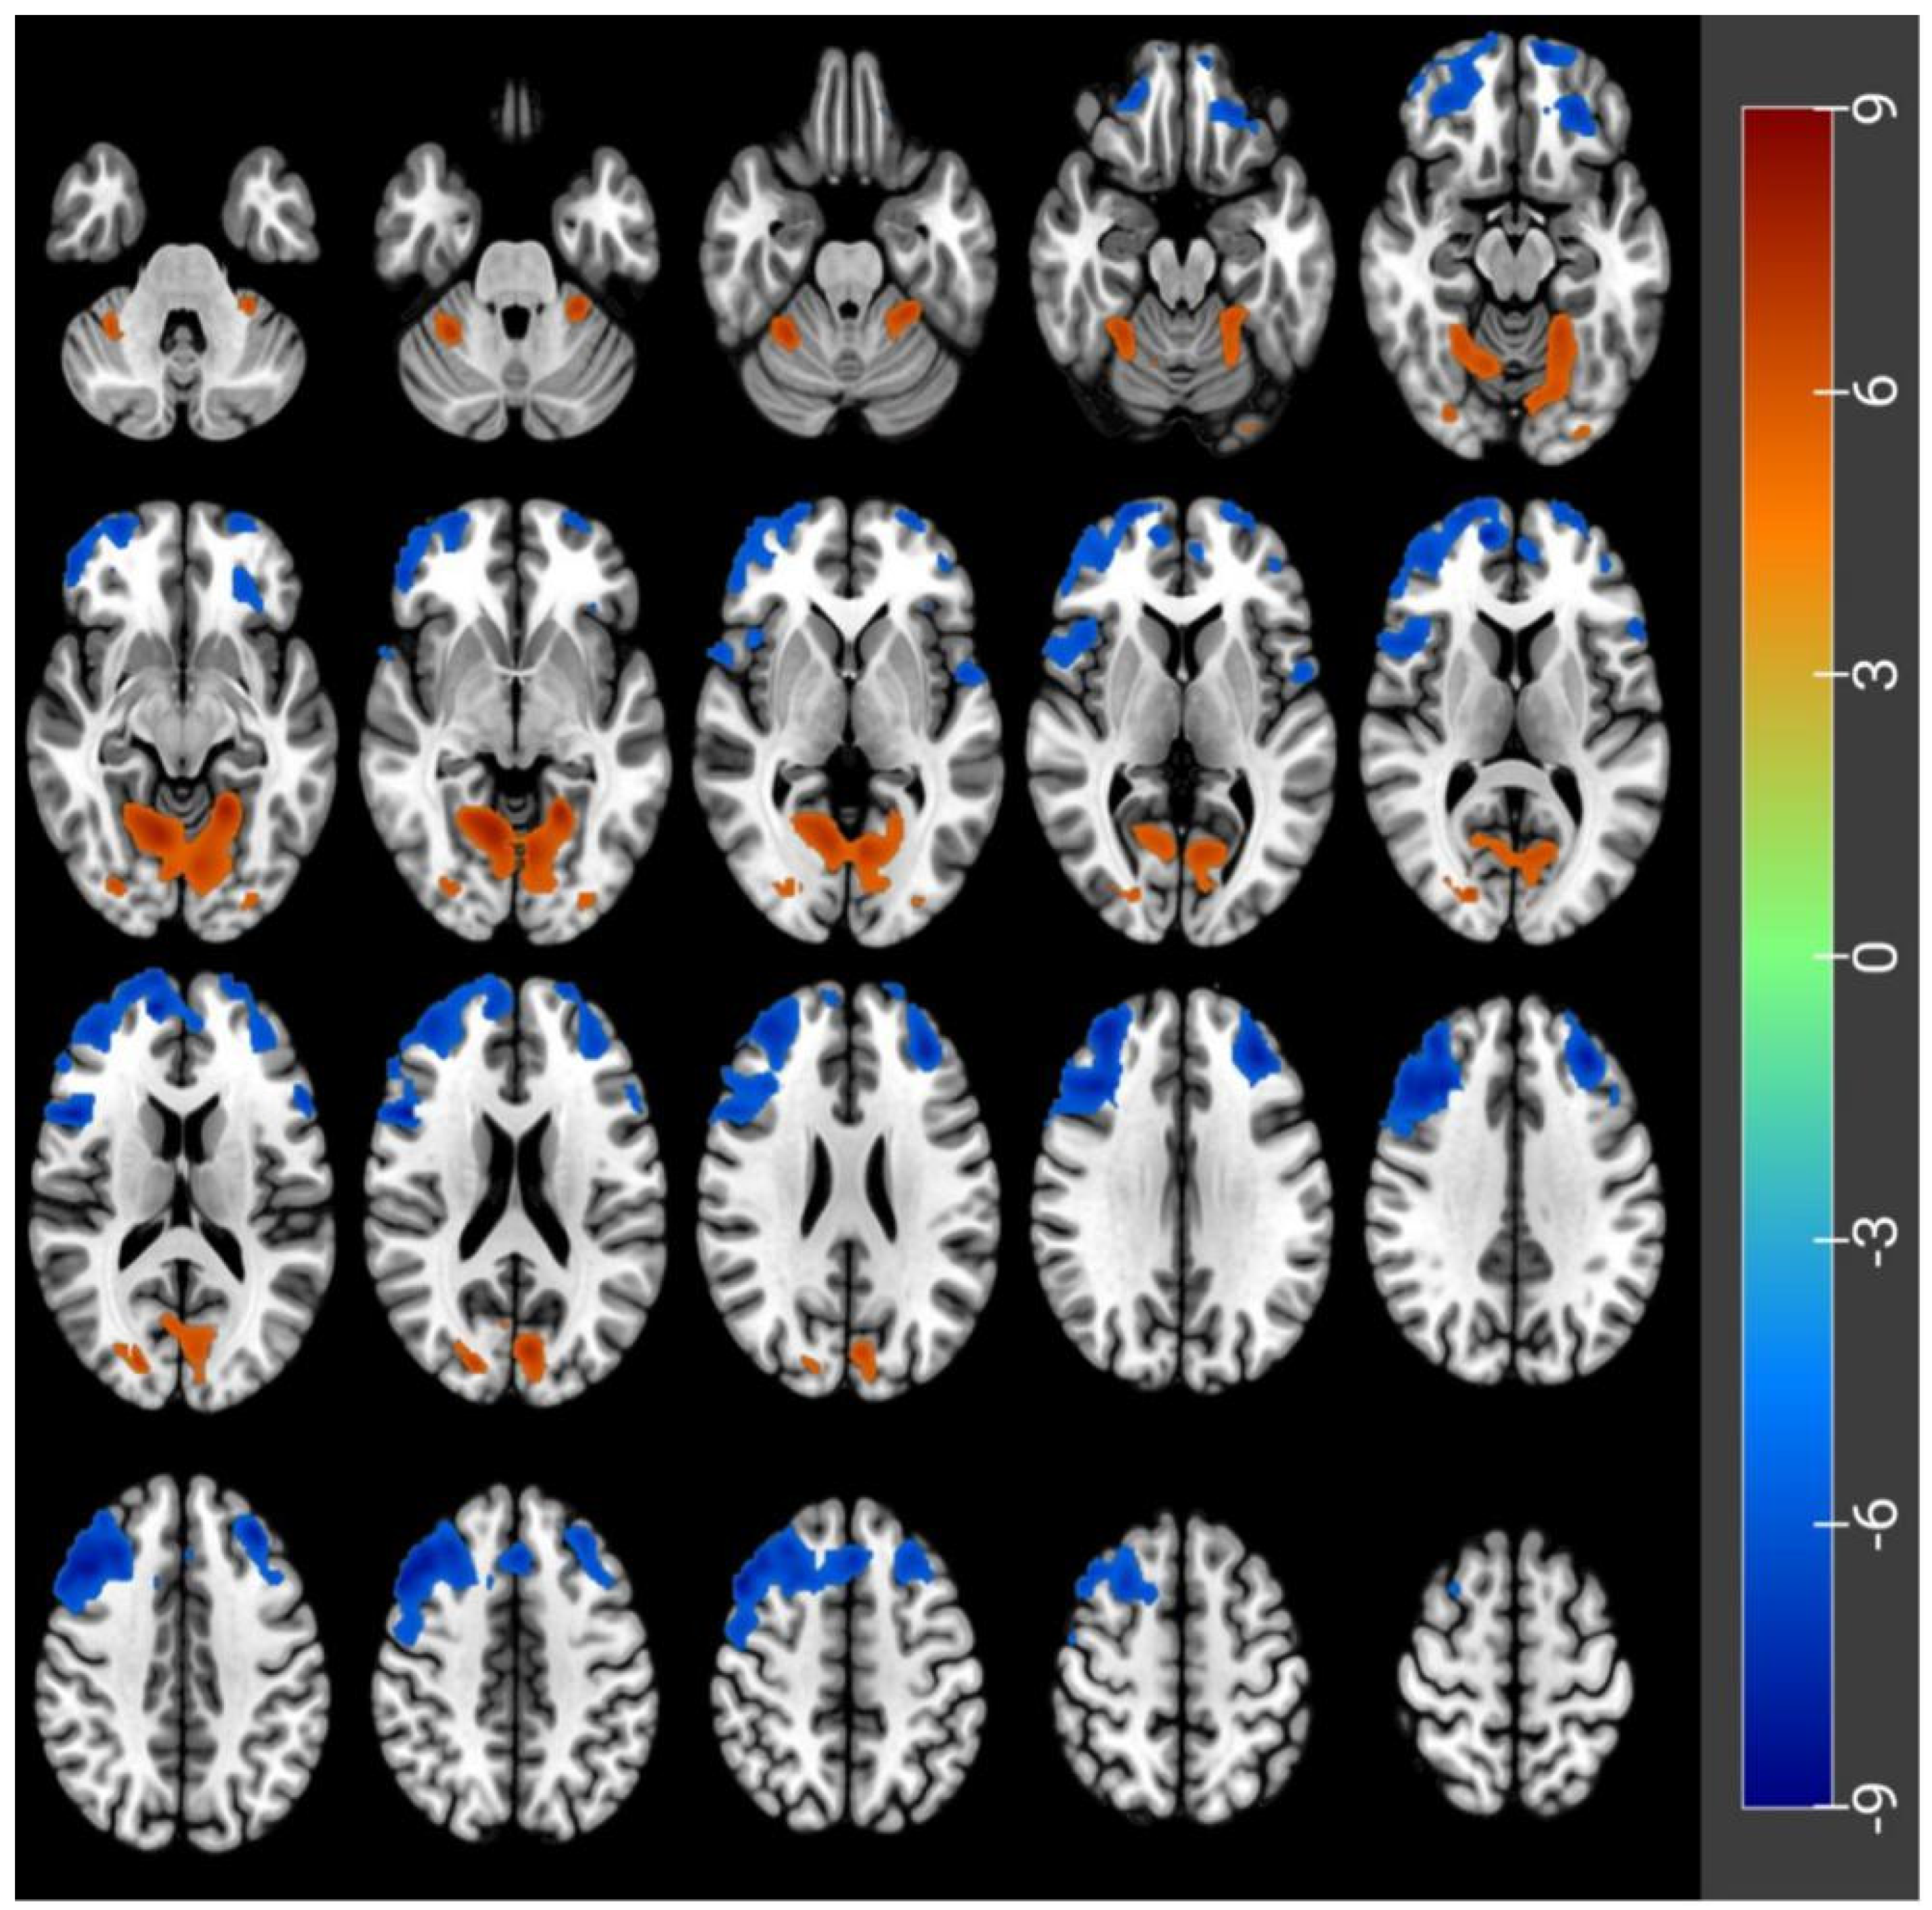

3.2. CBF Differences before and after Acute SD

| Peak Location | Side | Cluster Size | MNI Coordinates | Peak t-Score | p-Value Correctedby FWE | ||

|---|---|---|---|---|---|---|---|

| X | Y | Z | |||||

| Frontal_Mid_Orb | L | 372 | −26 | 40 | −18 | −7.2 | <0.05 |

| Frontal_Sup_Orb | L | 2006 | −12 | 62 | −18 | −9 | <0.05 |

| Frontal_Inf_Oper | R | 7735 | 48 | 14 | 18 | −8.56 | <0.05 |

| Frontal_Inf_Tri | L | 121 | −56 | 22 | 14 | −7.19 | <0.05 |

| Rolandic_Oper | L | 116 | −54 | 2 | 2 | −7.07 | <0.05 |

| Lingual | L | 3910 | −20 | −52 | −8 | 8.29 | <0.05 |

| Occipital_Sup | R | 346 | 20 | −84 | 18 | 7.06 | <0.05 |

| False Starts | Minor Lapses | Major Lapses | Mean RT | Fastest 10% RT | ||||||

|---|---|---|---|---|---|---|---|---|---|---|

| r | p | R | p | R | p | r | p | r | p | |

| Frontal_Mid_Orb_L | 0.25 | 0.22 | 0.26 | 0.19 | 0.30 | 0.14 | 0.29 | 0.15 | 0.10 | 0.63 |

| Frontal_Inf_Oper_R | 0.40 | 0.04 | 0.23 | 0.25 | 0.35 | 0.08 | 0.31 | 0.12 | 0.03 | 0.89 |

| Frontal_Sup_Orb_L | 0.41 | 0.04 | 0.32 | 0.11 | 0.21 | 0.31 | 0.34 | 0.09 | 0.16 | 0.45 |

| Frontal_Inf_Tri_L | 0.35 | 0.08 | 0.32 | 0.11 | 0.35 | 0.08 | 0.39 | 0.05 | 0.16 | 0.44 |

| Rolandic_Oper_L | 0.35 | 0.08 | 0.32 | 0.11 | 0.35 | 0.08 | 0.39 | 0.05 | 0.16 | 0.44 |

| Lingual_L | −0.38 | 0.05 | −0.26 | 0.20 | −0.50 | 0.01 | −0.39 | 0.05 | −0.09 | 0.67 |

| Occipital_Sup_R | −0.39 | 0.05 | −0.26 | 0.19 | −0.27 | 0.19 | −0.16 | 0.43 | 0.05 | 0.82 |